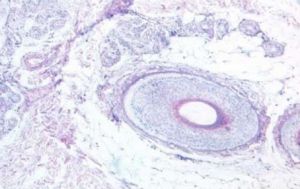

小汗腺腺體為管狀結構,有兩種腺體分泌細胞:透明細胞和暗細胞。前者內含豐富的糖原顆粒,主要分泌汗液,其中有較多的鈉離子、氯離子及少量糖原;後者含有充滿粘蛋白的空泡,分泌涎粘蛋白(故又稱粘液細胞),再吸收鈉、鉀、氯等電解質。透明細胞底寬而頂尖園,暗細胞底窄而頂寬,因此胞核不在同一線上,橫切面看似兩層細胞,實際上是單層柱狀或立方上皮。

此外,尚有肌上皮細胞散在相嵌於分泌細胞的基底部以支持分泌細胞,並迫使汗液輸送至皮面,其外圍為基底膜。真皮內蟠形導管與腺體分泌蟠管不同之處是無肌上皮細胞,管壁由兩層小立方細胞構成,其與腺體分泌蟠管盤繞在一起。小汗腺小葉的結構與功能與腎臟有些相似。真皮內直行導管自蟠形導管延續直行向上,貫穿真皮,延伸至乳頭內。表皮內導管自真皮內直形導管延伸而來,呈螺鏇狀穿越表皮,又稱末端汗管。末端汗管和末端毛囊(毛囊表皮內部分)一樣,在創傷修復中,可再生表皮。在表皮內的末端汗管呈螺鏇狀,易阻塞形成痱子。導管的特點是腔內襯有護膜。小汗腺受交感神經系統支配。